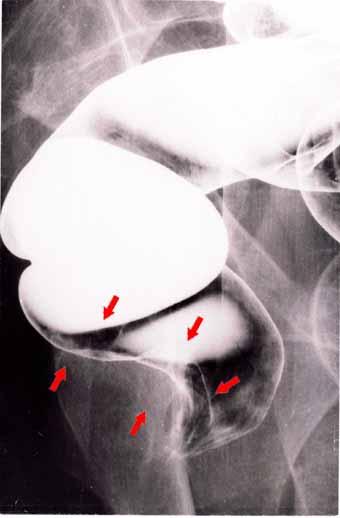

X선학적으로 보아 선암과의 감별이 곤란했던 직장부로부터 발생된 항문의 유기저세포암

악성 상피성종양/류기저세포암

대장/직장

X-P

2형(궤양국한형)/

40이상

ss(a1)